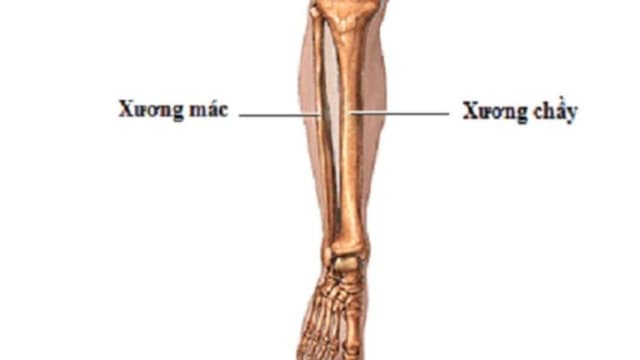

Những điều cần biết về gãy xương cẳng chân

Gãy xương cẳng chân là một trong những chấn thương phổ biến, đặc biệt là trong các hoạt động thể thao và tai nạn giao thông. Hiểu rõ về gãy xương cẳng chân sẽ giúp bạn nhận diện sớm và xử lý kịp thời khi gặp phải tình huống này. 1. Gãy xương cẳng chân […]